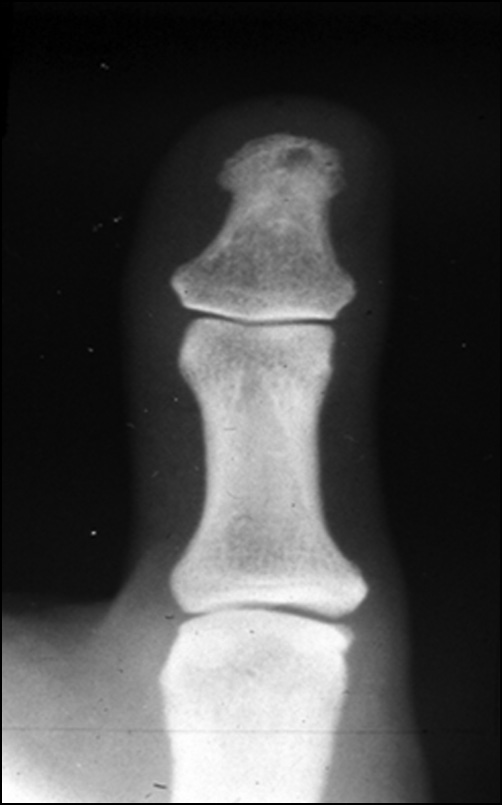

Типичная локализация как бы «выбитого пробойником» дефекта кости (рис. 7), а чаще — груботрабекулярная структура ногтевого отростка являются характерными рентгенологическими признаками гломангиомы. При расположении мягкотканного образования между двумя костями происходило смещение.

Рис. 7. Типичная локализация как бы «выбитого пробойником» дефекта кости при гломангиоме.

Fig. 7. Typical localization of a bone defect “punched out” by a glomangioma.